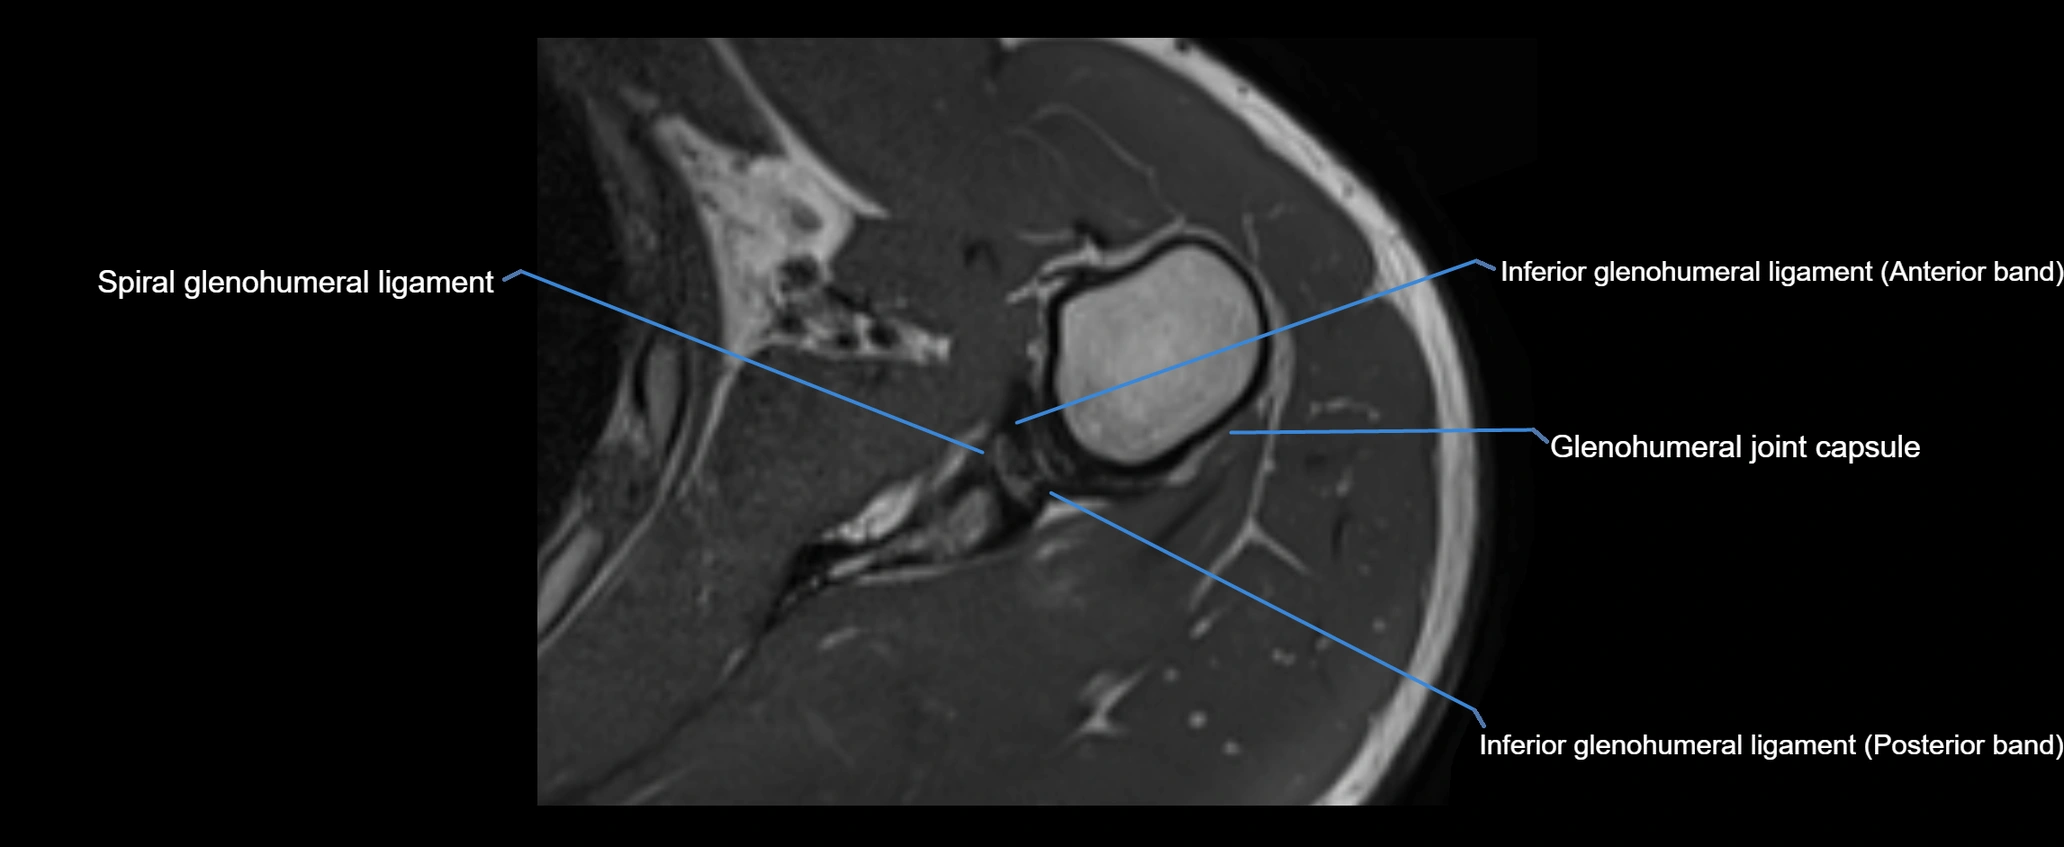

MRI images

image